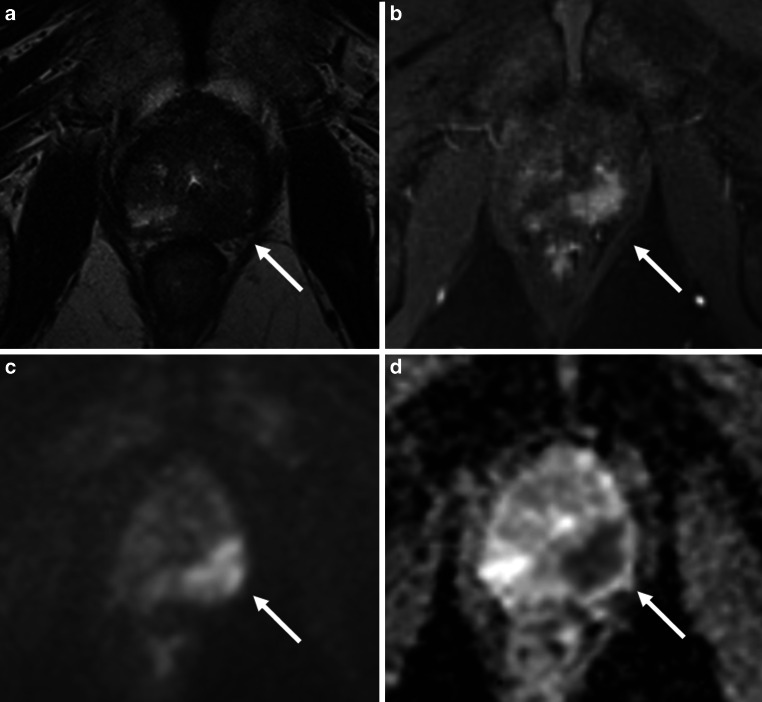

Methods: A retrospective analysis was conducted in patients with intermediate-risk prostate cancer undergoing robotic SBRT delivered in five fractions with a total radiation dose of 35-36.25 Gy. The primary endpoint was biochemical failure as defined by the Phoenix criteria. Among other clinicopathological data, T stage, Prostate Imaging-Reporting and Data System (PI-RADS) score, and multiparametric magnetic resonance imaging-based extra-prostatic extension (mEPE) score were collected and analyzed using the log-rank test.

Abstract Image